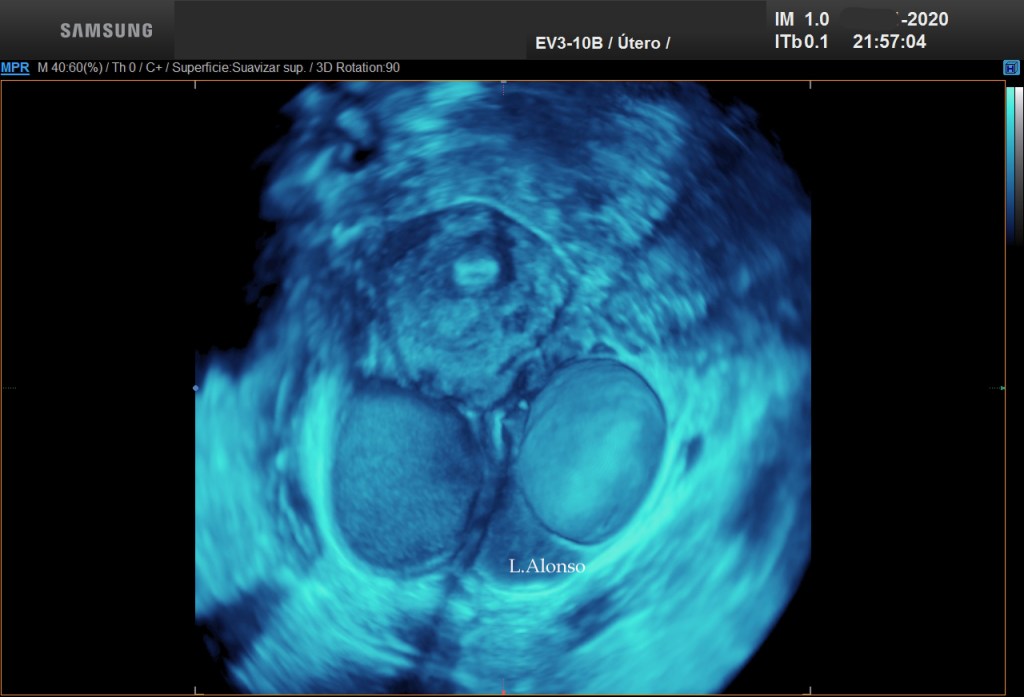

En determinadas ocasiones, los ovarios tienen quistes y se pegan entre sí detrás del útero, es lo que se conoce como «kissing ovaries». Esto es un signo ecográfico de la existencia de una endometriosis severa

Dr. Luis Alonso